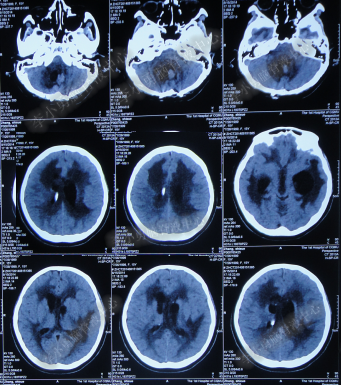

腰大池持续引流20天内,体温仍间断高热,曾3次脑脊液细菌培养均示鲍曼不动杆菌,先后使用利奈唑胺+克倍宁,利奈唑胺+克倍宁+奥硝唑,舒普深+米诺环素+来立信+氟康唑,舒普深+米诺环素+美罗培南+氟康唑,及日达仙、人免疫球蛋白提高免疫力,但颅内感染仍控制不住,期间多次头部CT检查均示脑室无明显扩张(图-7、图-8、图-9)。

图-7:2014年6月9日头部CT

图-8:2014年6月14日头部CT

图-9:2014年6月21日头部CT